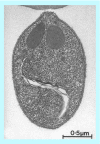

Figures